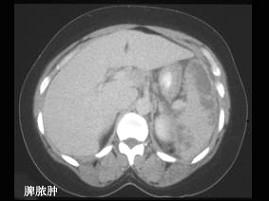

选项 A、脾脏脓肿 B、脾血管瘤 C、肝硬化并发脾肿大 D、某些血液疾病 E、外伤性脾破裂

答案 ABCDE